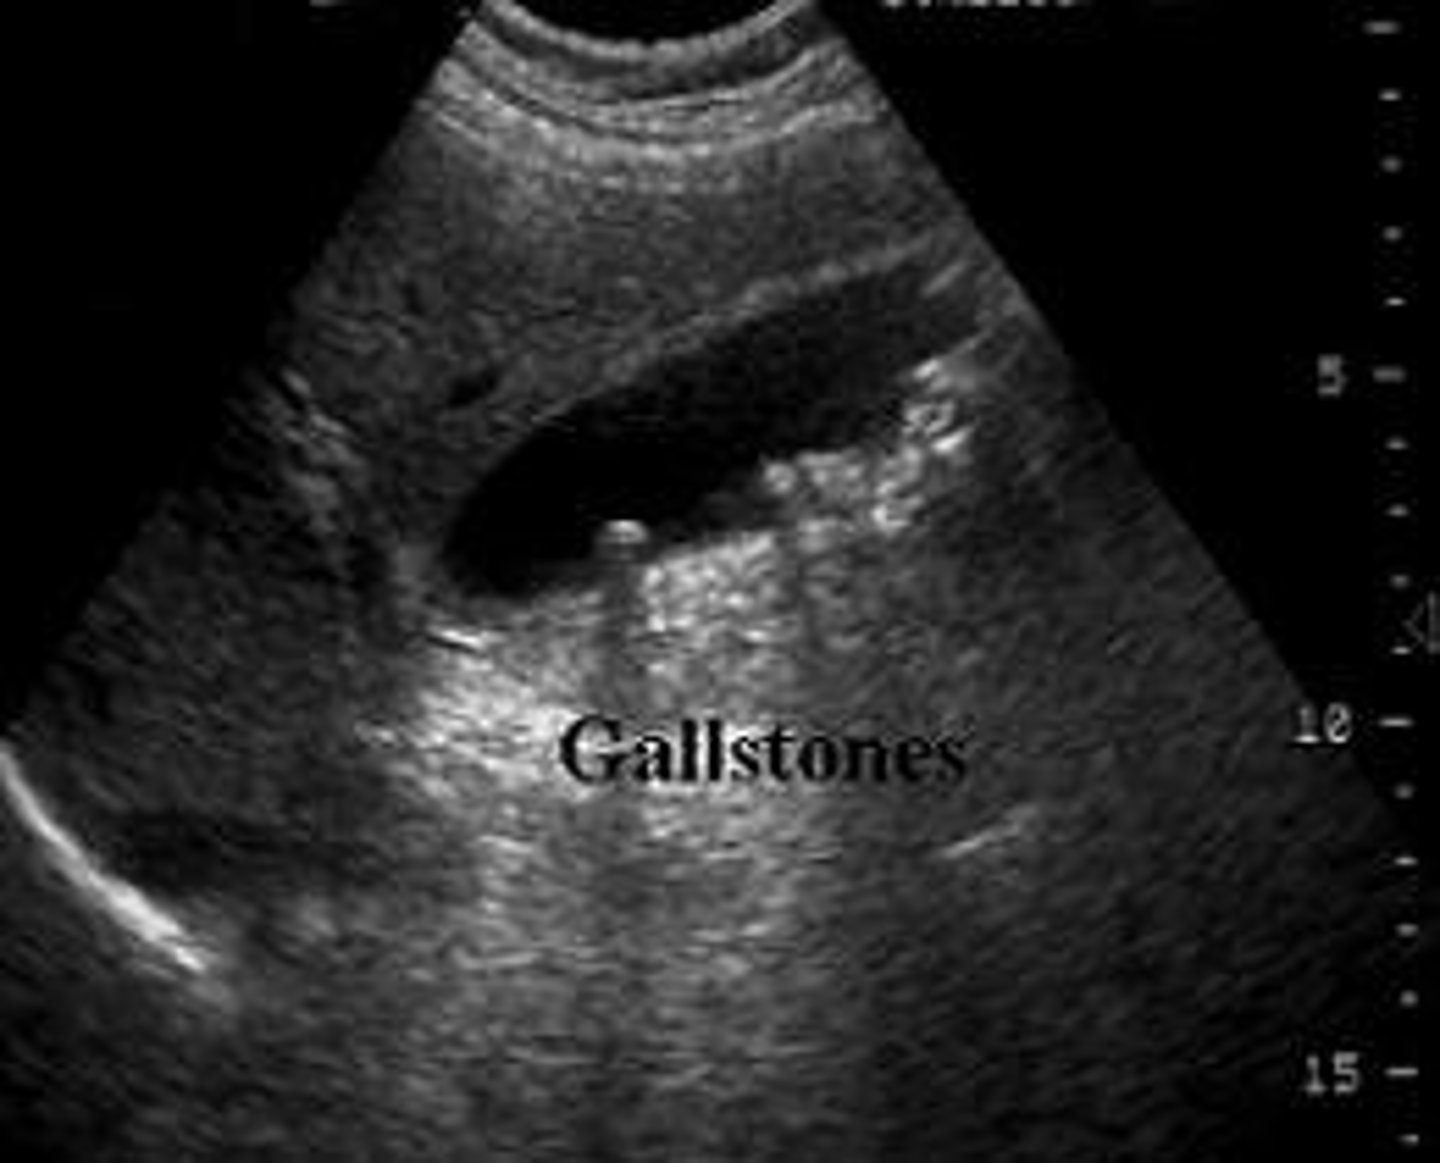

What are diagnostic ultrasounds used for?

View organs & evaluate motion (cardiology, OBGYN, GI, & vascular medicine)

Diagnostic ultrasound

Echoes of the US beam bounce off interfaces between tissues with different acoustic properties

-Sends high-frequency sound into patient & assesses strength & time of returning echoes

-Echoes caused by changes in density

What are ultrasounds used for?

Obstetrics, cardiology, vascular, abdominal

US advantages

Inexpensive, non-invasive, no radiation

US limitations

Quality is technician-dependent

-Pt body habitus

Ultrasounds can also be used for procedure guidance. Give 2 examples of US-guided procedures.

1. Thoracentesis

2. Biopsy (needle placement)